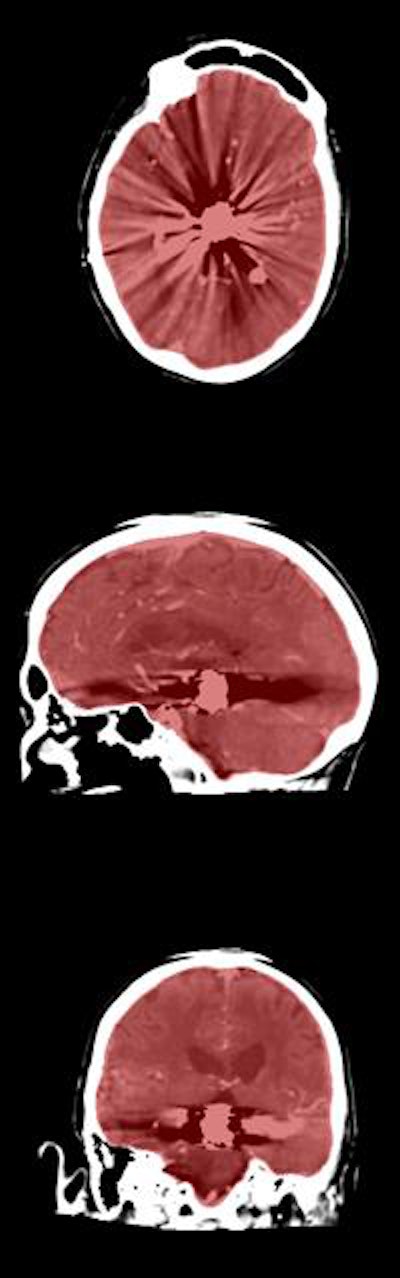

In their study, the researchers developed a way to use software to automatically segment the cranial cavity based on anatomy borrowed from multiple image atlases, then refined the segmentation based on the patient's head CT data. The results closely correlated with manual segmentation of the cranial cavity in CT studies, validating the approach in a database of almost 600 patients.

Prior images in the atlas are registered to the patient image using a two-staged approach, Patel said. The first is an affine registration for a coarse alignment of the images, followed by a second, nonlinear registration to deform the atlas labels to fit the patient image. The method described is used to obtain a segmentation of the entire cranial cavity and does not differentiate between healthy or ischemic regions within the brain parenchyma. The segmentation serves as an initial step in the development of algorithms to detect and quantify anatomical regions and pathology within the cavity.

Labels for the registered atlas are then fused to create an initial approximation of the patient's cranial cavity, which is used to create a multistage geodesic active contour levelset method, where levelset represents an evolving surface steered by image information.

The gradient at the inner edge of the skull served as a boundary to stop propagation of the segmentation process. The first stage of refinement enables correction of errors that might be introduced during image registration while also allowing fast propagation of the initial segmentation. The second stage refines segmentation along the inner boundary of the skull.

The multiatlas registration results showed a high degree of overlap with the reference standard, yielding a mean Dice similarity coefficient of 0.973 ± 0.035, and adding levelset refinement increased the value to 0.984 ± 0.026.

The results encompass a large spectrum of anatomical and pathological variations seen in everyday clinical practice, and they closely approach the high performance of expert manual annotation, the authors wrote.